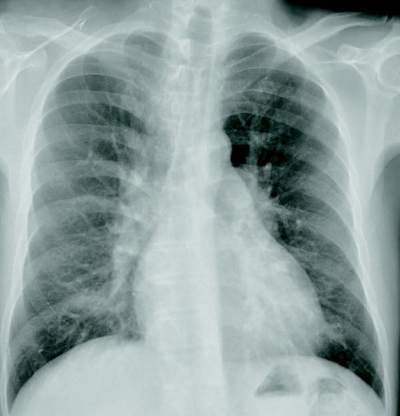

心音はII音の固定性分裂を認め、胸骨左縁第2肋間に収縮期雑音を聴取する。呼吸音に異常を認めなぃ。下肢に浮腫を認めない。手指にチアノーゼ、ばち指を認めない。心電図は洞調律で不完全右脚ブロックを認める。胸部エックス線写真及び心エコー図を別に示す。その後心臓カテーテル検査を行った。

この患者の各部位の酸素飽和度(%)で正しいのはどれか。

(SVC:上大静脈、RA:右心房、RV:右心室、PA:肺動脈、LV:左心室)